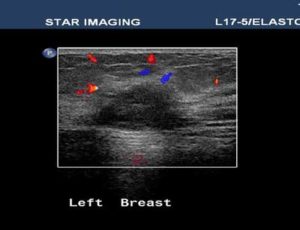

39yr old lady with history of lump in the left breast UIQ, No previous imaging done. No positive family history for CA Breast/Ovary. Pre-Menopausal Status.

Mammography- Fairly well circumscribed predominantly sold lesion in the left breast UIQ with partially obscured margins. No spiculations. No associated microcalcifications noted. Sonography: Well defined hypoechoiec lesion with smooth margins.